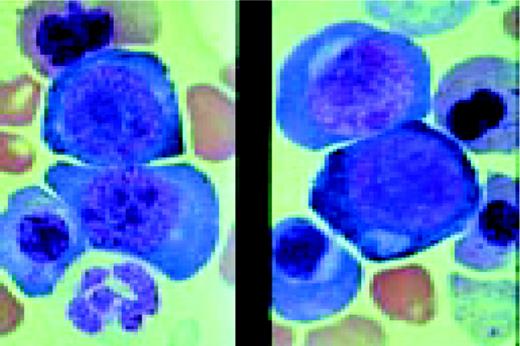

Slide L14

Prolymphocytic leukemia (PLL). This composite slide shows prolymphocytic leukemia (PLL) from two different patients. On the left is B cell PLL and on the right, T cell PLL. The B-PLL cells correspond to the classic description of Galton et al. (Br J Haematol 27:7, 1974): They are larger than CLL lymphocytes, have condensed chromatin, and have prominent large nucleoli. The T-PLL cells have a less conspicuous nucleolus, an irregular nuclear outline, and cytoplasmic blebs, as described by Matutes et al. (Blood 78:12, 1991). In many cases it may (FIX) be difficult to distinguish B-PLL from T-PLL cells on morphologic grounds alone, without performing additional immunophenotypic studies.FIG14